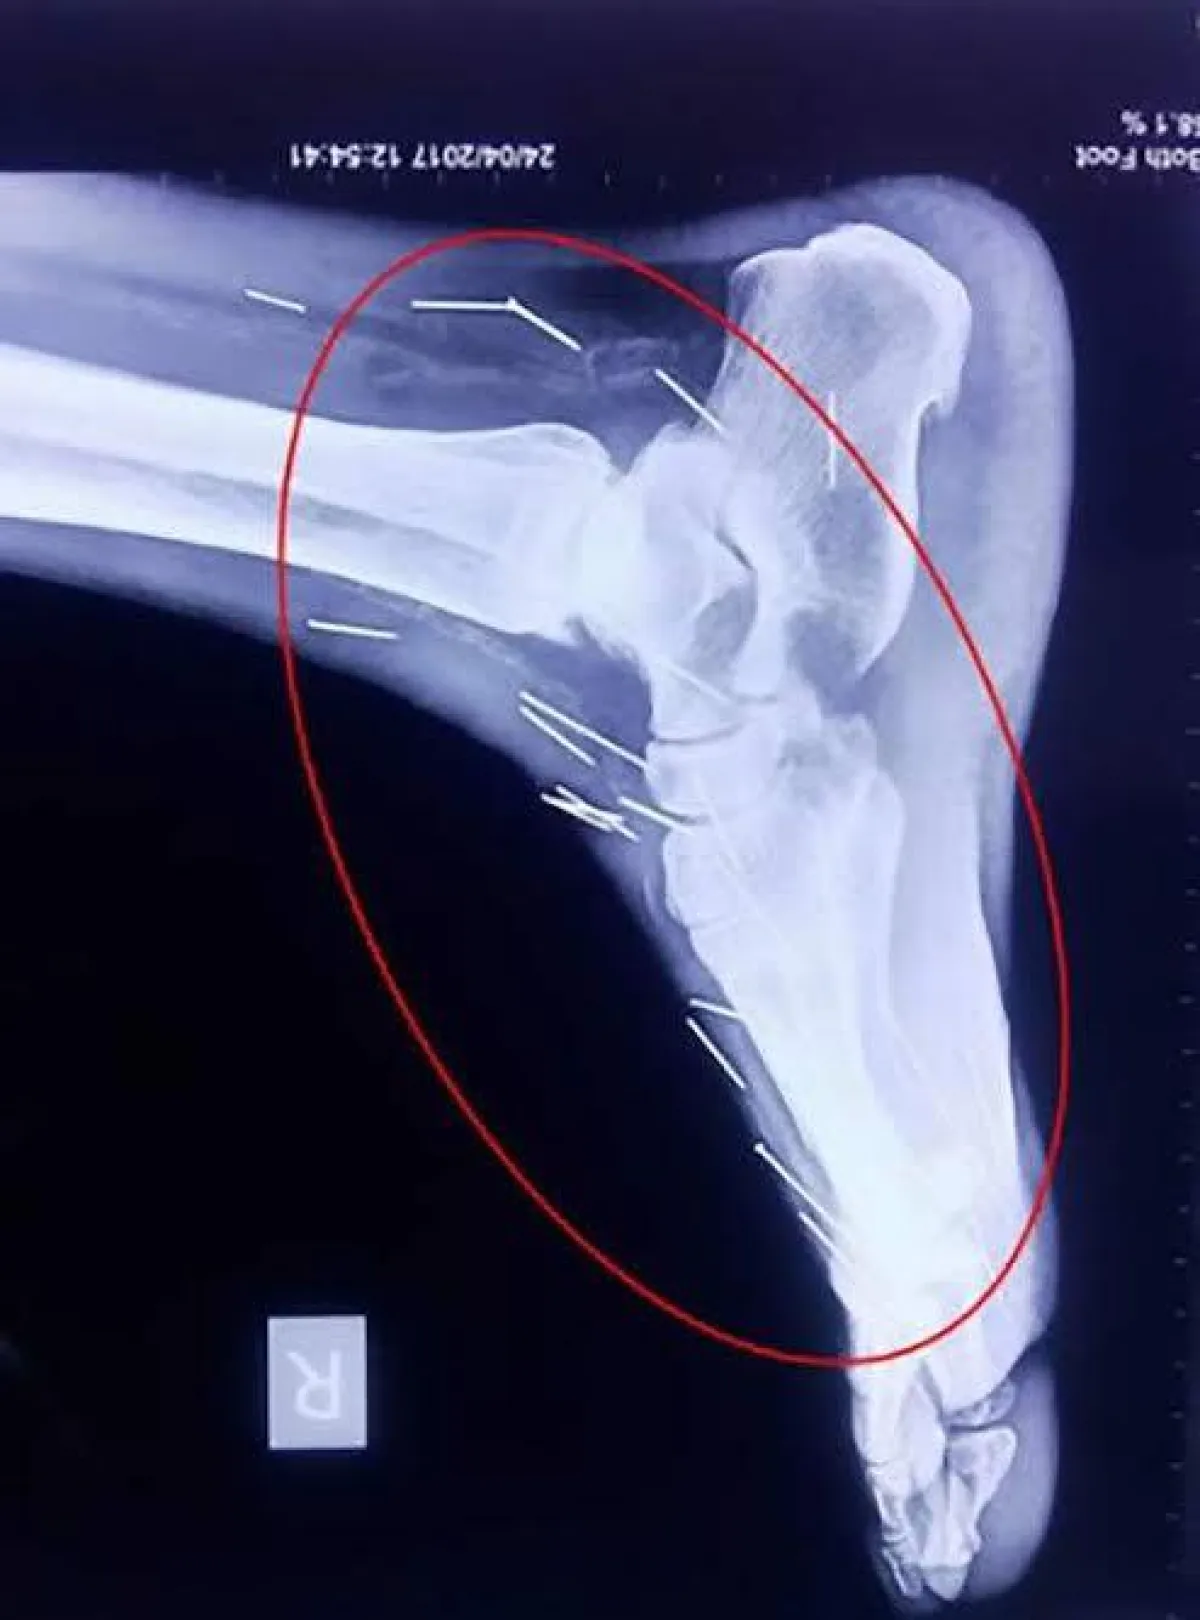

وطبقا لموقع "ديلي ميل"، عانى رجل هندي يدعى "بدريلال مينا" (56 عاماً) من آلام في قدمه، وعندما ذهب للمستشفى أكتشف الأطباء وجود مسماراً بداخل قدمه يتسبب في تلك الآلام، وكانت المفاجأة عندما قام الأطباء بإجراء أشعة سينية على جسده ليكتشفوا أن هناك 75 مسماراً داخل أماكن متفرقة من جسده دخلت بشكل متعمد .

ويرقد الرجل حالياً في مستشفى "مومباي" استعداداً لإجراء الجراحة، التي سيتم خلالها ازالة 40 مسمار من الحلق و 25 من ساقه اليمنى و10 من أماكن متفرقة باليدين وباقي الجسد .